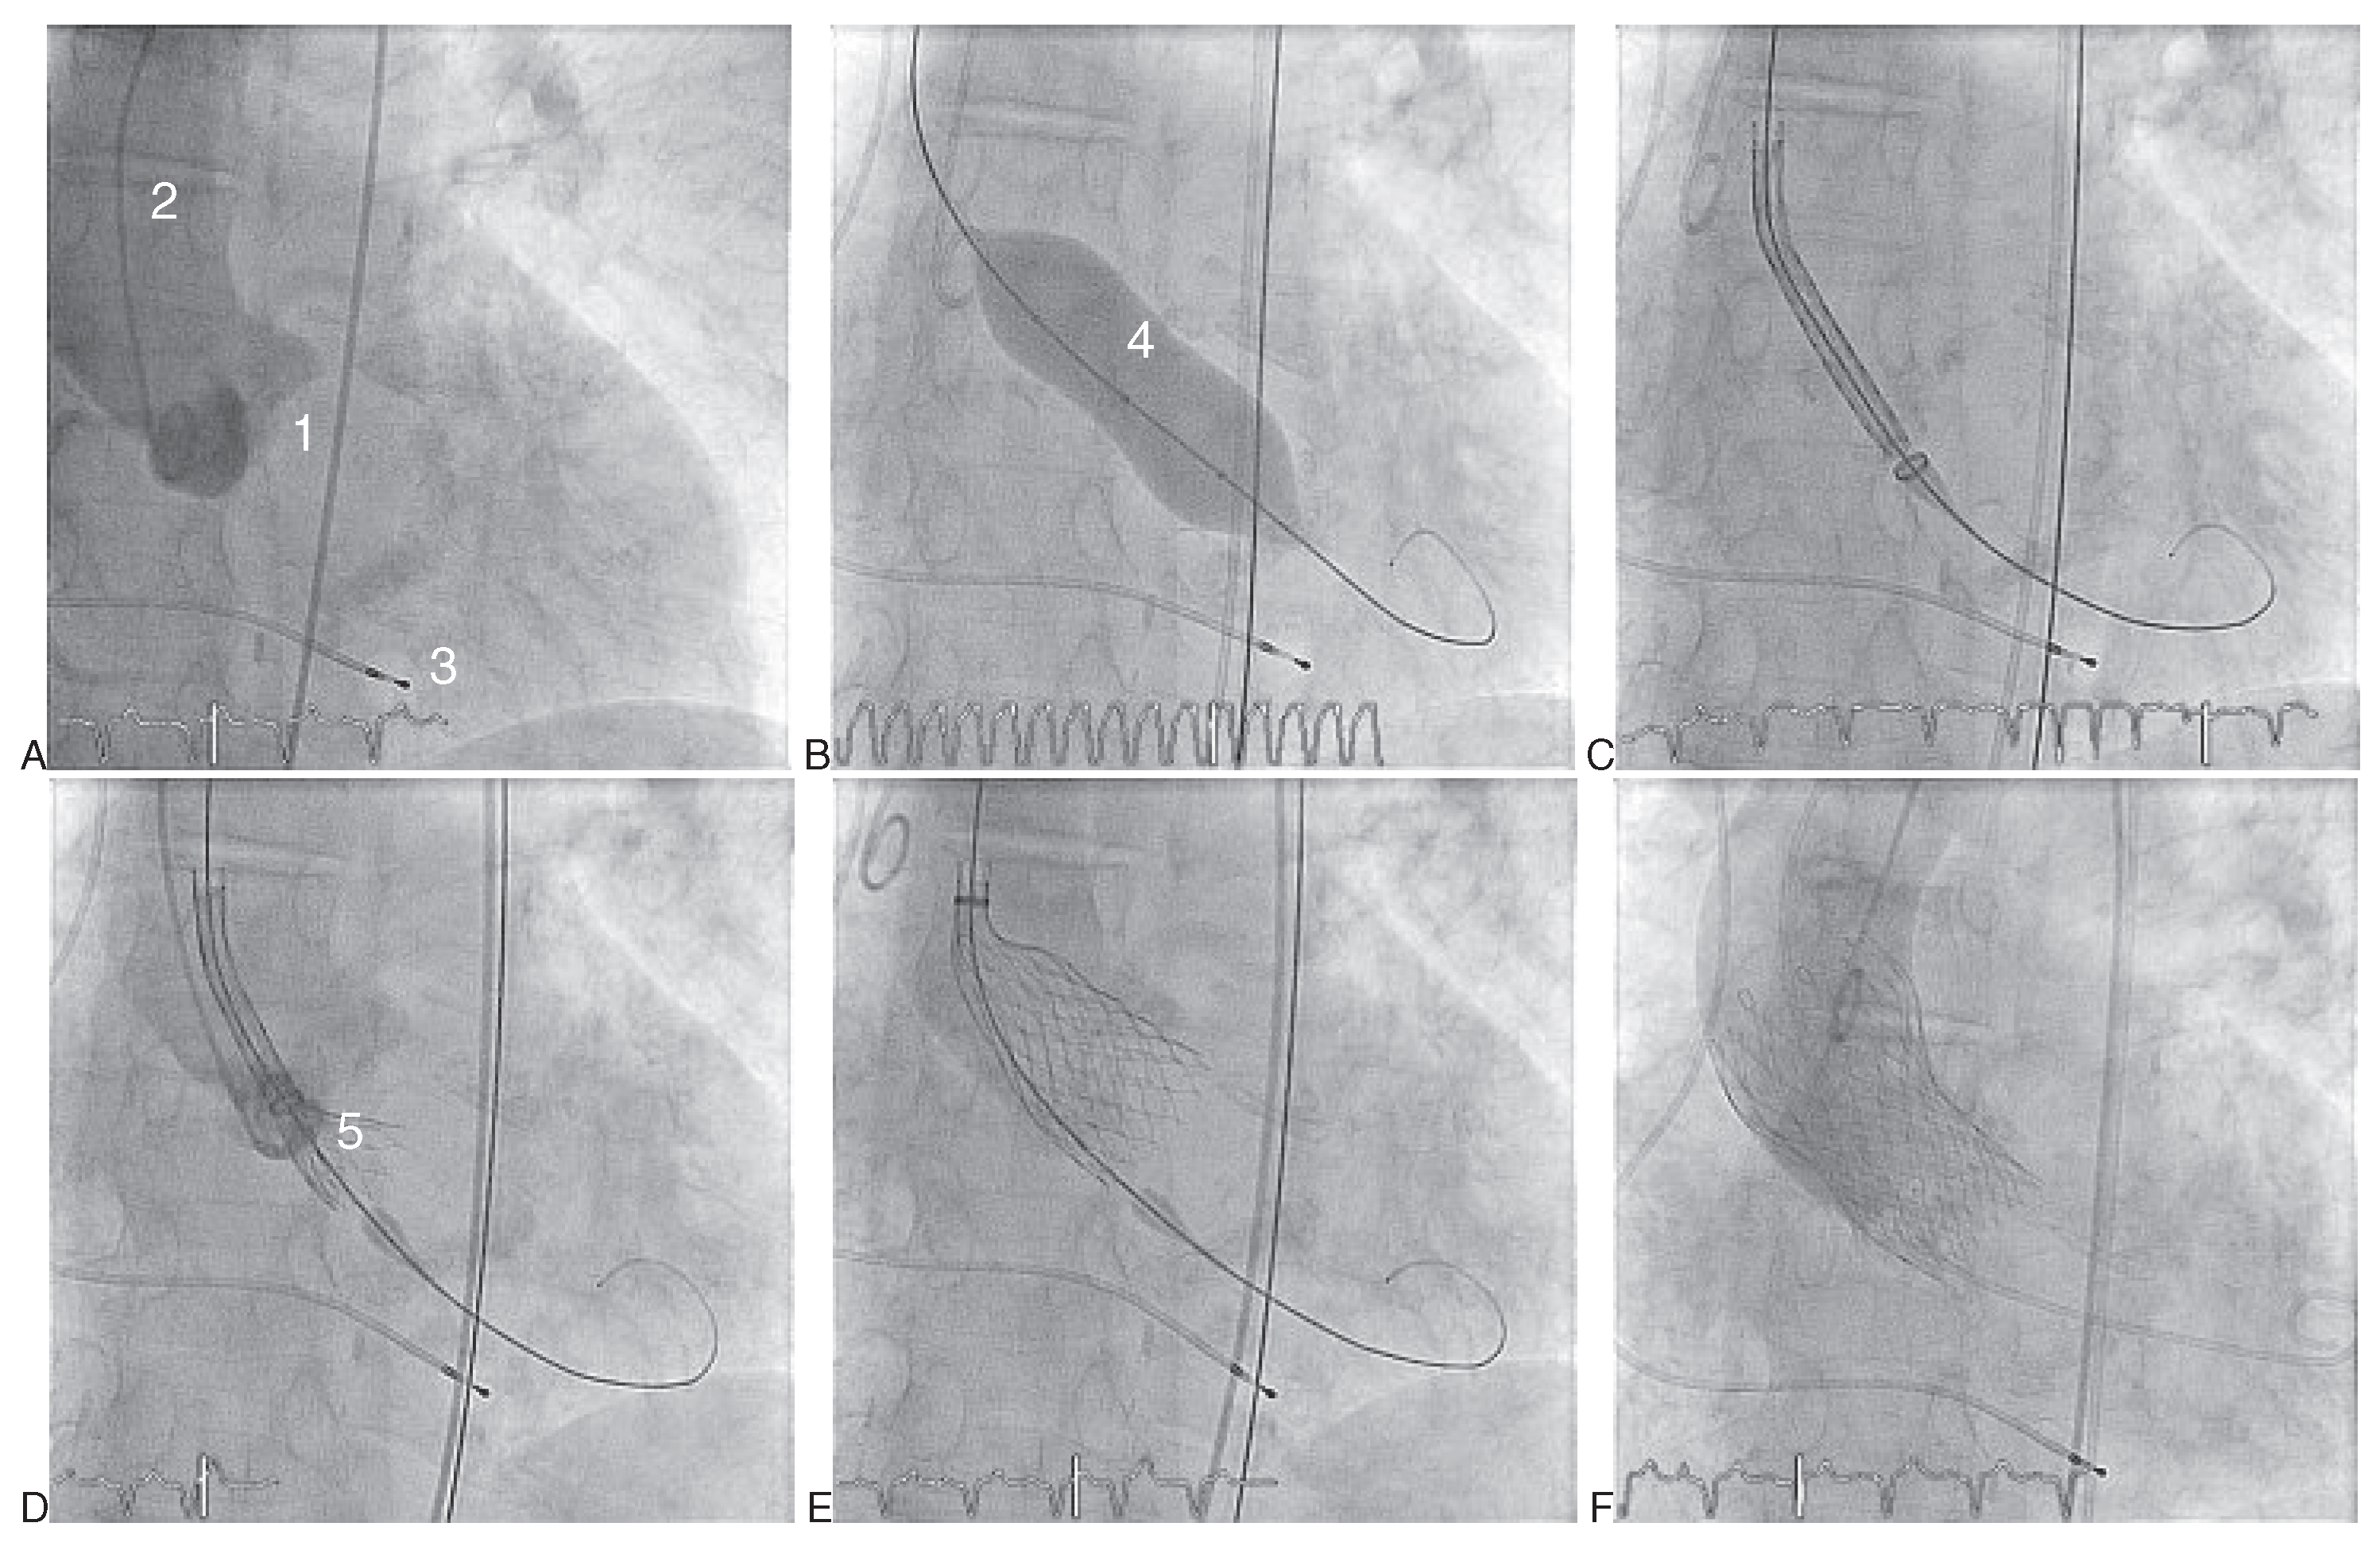

Abbildung 4. Transfemorale Implantation einer Medtronic CoreValeve Bioprothese (AF). (A) Aortographie. (B) Vordilatation unter rapid pacing. (C) Positionierung des Einführungskatheters mit der geladenen Klappe im Aortenannulus. (D,E) Selbstständige Expansion der Medtronic-CoreValve-Prothese nach Zurückziehen der Hülle. F Kontrollaortographie nach Implantation der Bioprothese und Entfernen des Einführungskatheters. 1 Aortenklappenannulus; 2 Pigtail-Katheter; 3 Provisorische Schrittmachersonde im rechten Ventrikel; 4 NuMed-Nucleus-Ballon zur Vordilatation; 5 CoreValve-Bioprothese auf Einführungskatheter geladen; 6 Vollständig entfaltete Klappenprothese.